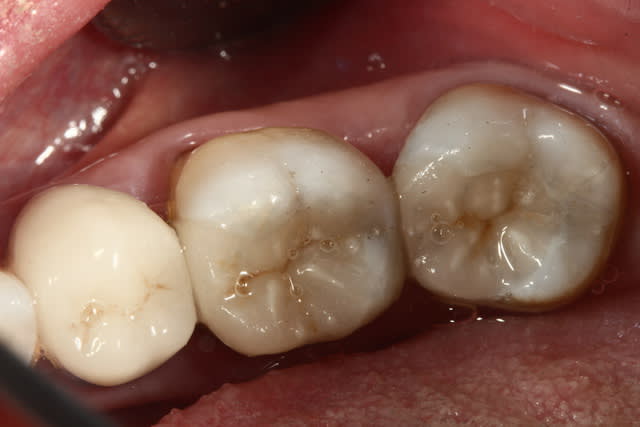

Photo 1. Moi: "Voilà pourquoi il vous faut un onlay."

Photo 3. Le patient: "Ah quand même! Ben on va faire les autres alors!"